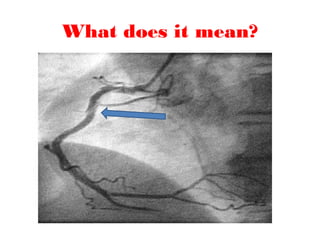

What does it mean?

Spontaneous coronary artery dissection